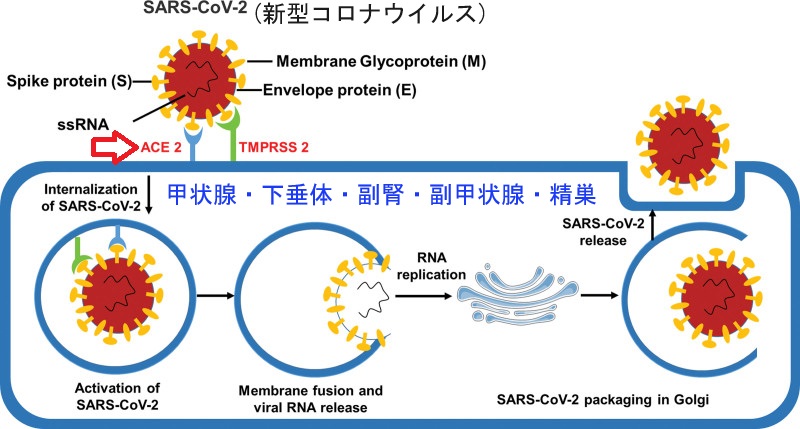

また、新型コロナウイルス(severe acute respiratory syndrome coronavirus 2:SARS-CoV-2) が結合し、増殖するのに必要な細胞膜結合酵素アンジオテンシン変換酵素2[ACE-2]は、甲状腺・下垂体にも発現しています。(Infect Dis Poverty. 2020 Apr 28;9(1):45.)

[図;Medicine (Baltimore). 2022 Jul 8;101(27):e29401.より改変]

また、新型コロナウイルス(SARS-CoV-2) が結合し、増殖するのに必要な細胞膜結合酵素アンジオテンシン変換酵素2は、甲状腺にも発現しています(発現していないとの意見もあり)(Infect Dis Poverty. 2020 Apr 28;9(1):45.)。しかし、現時点で、これらの甲状腺機能異常が新型コロナウイルス(SARS-CoV-2)による直接的な甲状腺の破壊で起きる証拠は報告されていません。